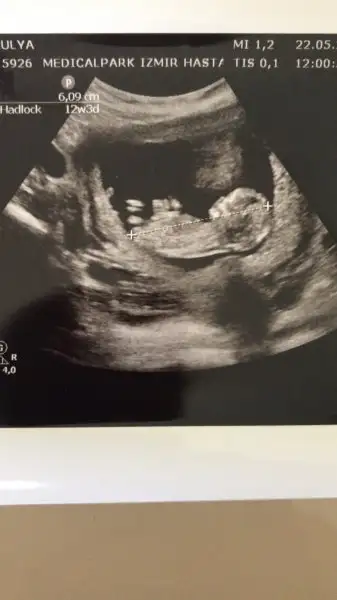

Erkek gibi dedi ama 16 haftayı bekliyorum cnmBenimkine benziyor bakalım belli olunca söyler misin bana daha cok var belli olmasına

Cnm nub teorisi diye arastır istersen bir orda daha net belki fikrin olur allah gönlündekini versin inş ama sanırım bu 2018 de herkes daha bir kız istiyor ben de dahil sağlıklı olsunlar daBenim ki kız mu erkek mi?

Teşekkür ederim sonra gördüm oraya da ekledim. Evet benim iki erkekten sonra bir kız istemem çok doğal umarım Allah gönlümüze göre verirCnm nub teorisi diye arastır istersen bir orda daha net belki fikrin olur allah gönlündekini versin inş ama sanırım bu 2018 de herkes daha bir kız istiyor ben de dahil sağlıklı olsunlar da

Teşekkür ederim biz olduk 12+2 nub yorumlayabiliyor musun?Kız gibi cnm

Onu tam secemiyorum yani anlamiyorum canım bu teoriyi bile pek bilmiyorum kendimce yorum yapıyorum canımTeşekkür ederim biz olduk 12+2 nub yorumlayabiliyor musun?